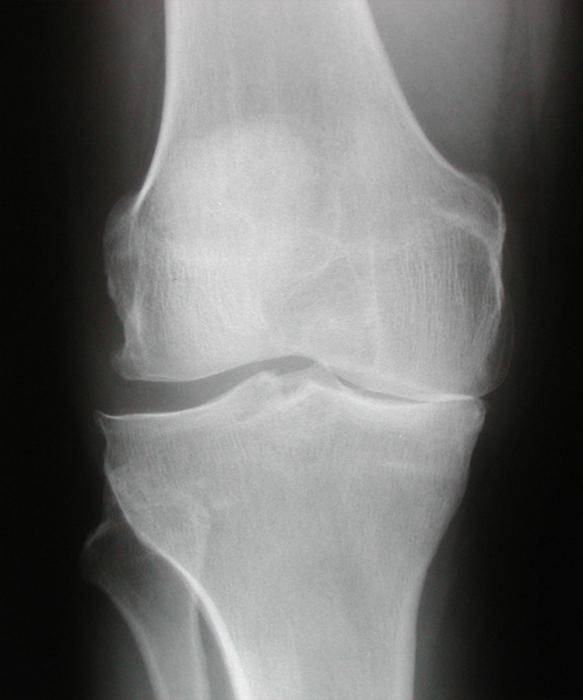

Наиболее четкую картину можно увидеть на рентгенографических снимках. Деформирующий гонартроз коленного сустава второй степени характеризуется специфическими краевыми разрастаниями и сильным сужением щели.